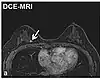

| Dynamic contrast enhanced | DCE | Measures changes over time in the shortening of the spin–lattice relaxation (T1) induced by a gadolinium contrast bolus.[84] | Faster Gd contrast uptake along with other features is suggestive of malignancy (pictured).[85] | ![]() | |